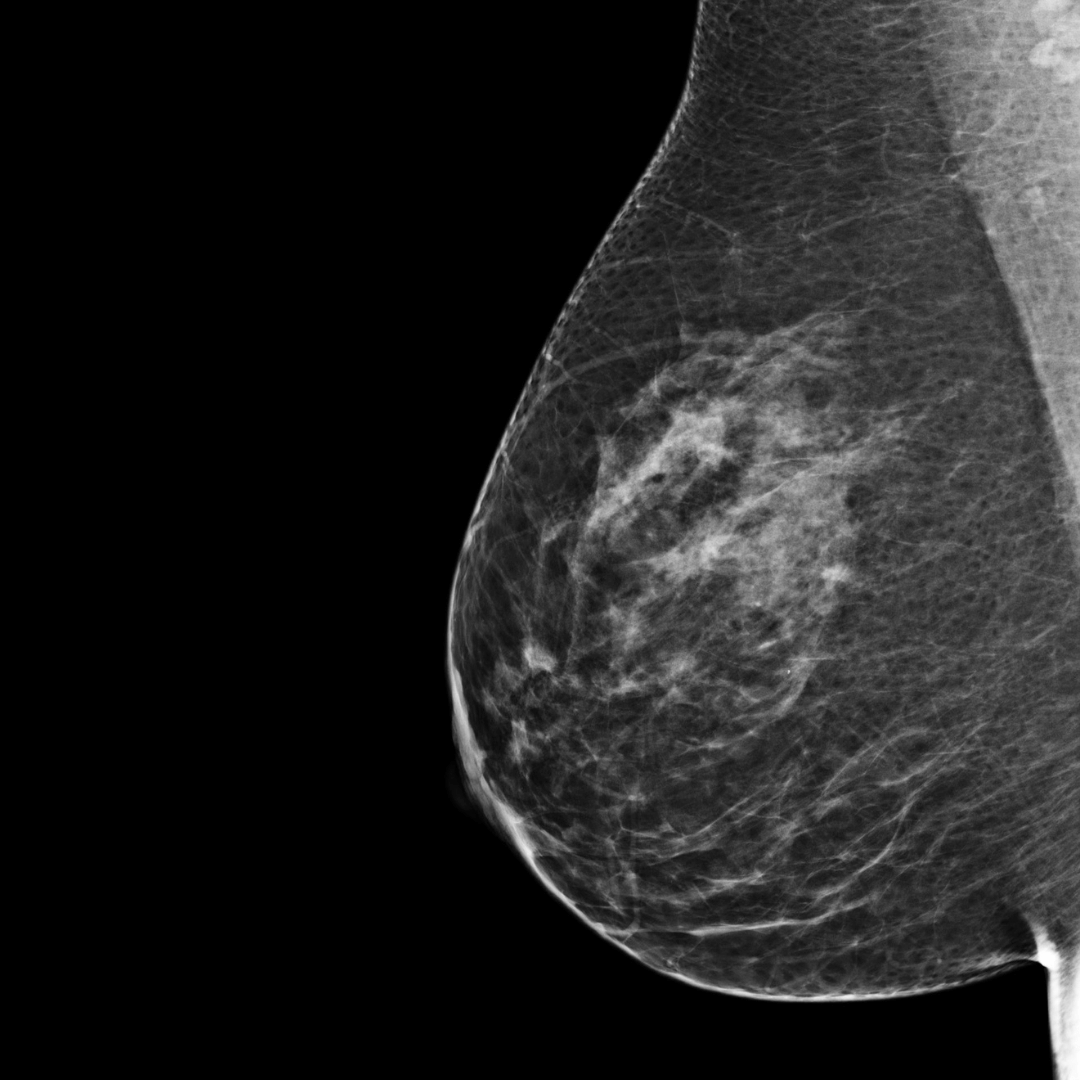

Category B

BI-RADS category B:

The breast tissue is mostly fatty tissue with some scattered areas of

fibroglandular density. The breast tissue is not dense.